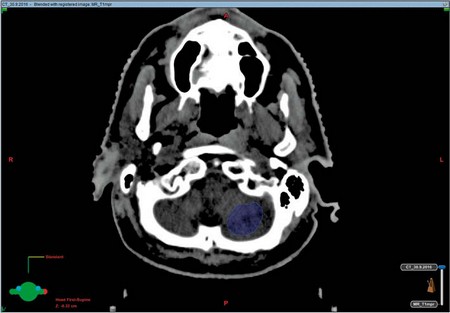

Mezitím ovšem začíná další část procesu pro lékaře radioterapeuta – zakreslení kontur cílových objemů a kritických struktur do plánovacích CT snímků, jejich fúzování s MR pro lepší orientaci a rozlišení v měkkých strukturách (obr. 8, 9).

Obr. 8, 9 – Fúze snímků plánovacího CT a MR vyšetření